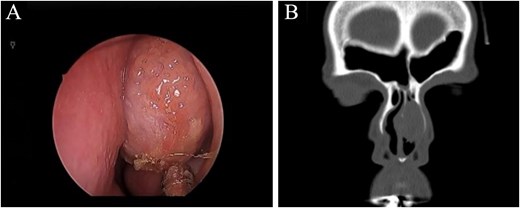

A rigid endoscopic examination of the nose showed a unilateral nasal mass originating from the left nasal septum (Fig. 1A). The mass was found above the inferior turbinate and anterior to the middle turbinate, the mass was compressible and bloody on touch. Other otolaryngological examinations were unremarkable, and there were no palpable cervical lymph nodes.

(A) Nasal endoscopic examination showing left nasal septal mass. (B) Computed tomography scan of the paranasal sinuses showing a focal soft tissue lesion arising from the left deviated nasal septum, causing thinning of the left nasal bone measuring 2.2 × 1.7 × 2.7 cm.

A computed tomography (CT) scan without contrast of the paranasal sinuses showing a focal soft tissue lesion arising from the left deviated nasal septum, causing thinning of the left nasal bone measuring 2.2 × 1.7 × 2.7 cm (Fig. 1B).